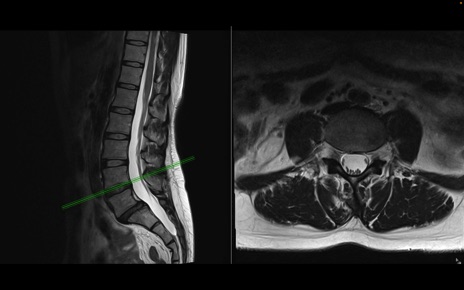

腰椎MRI

T2WI(横断像)

T2WI(矢状断像)